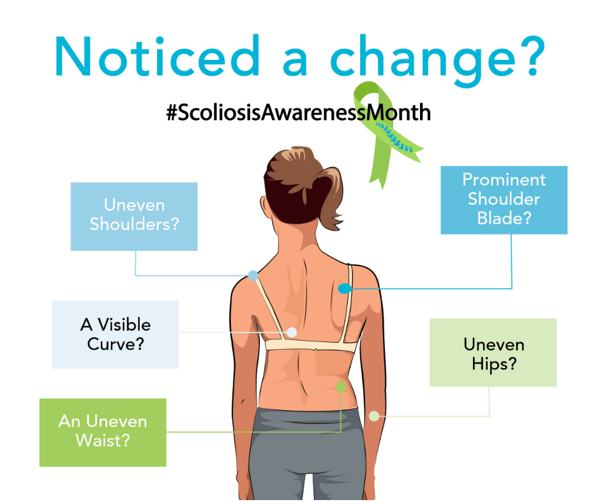

Worried About a Loved One’s Spine?

Early signs of scoliosis shouldn’t be ignored —act with confidence.

Are you noticing signs of scoliosis in your loved one or child? Uneven shoulders, a visible curve in the spine, or poor posture could be early indicators.

Taking action early can make a big difference—but choosing a safe and effective solution is even more important.

That’s where ScoliBrace comes in: a proven, non-surgical treatment designed to correct and manage scoliosis with comfort and precision.

Diagnosing scoliosis involves a thorough assessment of the patient and analysis of some specific test results. The first step involves taking a thorough medical history to ensure we have the details required before starting the physical examination. The history can provide us with some vital information towards guiding a diagnosis.

After that we start the physical assessment of the patient. This includes a variety of observations and measurements, including posture and movements, as well as conducting some very important standardised tests of the musculoskeletal and nervous systems.

The final part of the assessment will involve analysis of X-rays and, where required, other radiological scans. Together with the history and assessments the radiological information and measurements can give us vital information to finalise a scoliosis diagnosis and classification. When patients have not yet had any X-rays or other scans, we can provide recommendations if necessary.